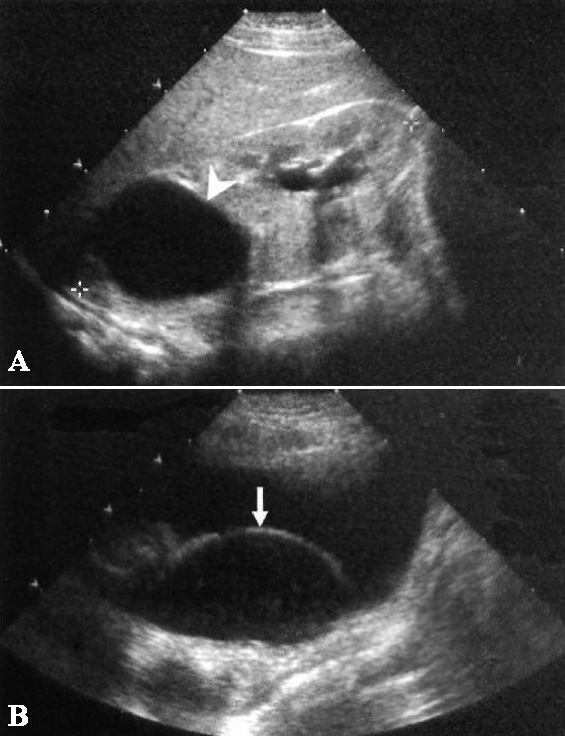

Если ультразвуковое исследование демонстрирует удвоение собирающей системы с гидронефрозом верхнего полюса, значит в мочевом пузыре нужно искать уретероцеле (фото 4).

Фото 4. Гидронефроз и уретероцеле. А – продольное ультразвуковое изображение правой почки у ребенка: указателем отмечен выраженный гидронефроз верхней половины удвоенной почки. Также нужно обратить внимание на незначительное выпячивание центрального отдела собирающей системы нижней половины, обусловленное везикоуретеральным рефлюксом (закон Вейгерта-Мейера). В – поперечное ультразвуковое изображение мочевого пузыря того же больного: стрелкой обозначено большое обструктивное уретероцеле, исходящее справа от срединной линии